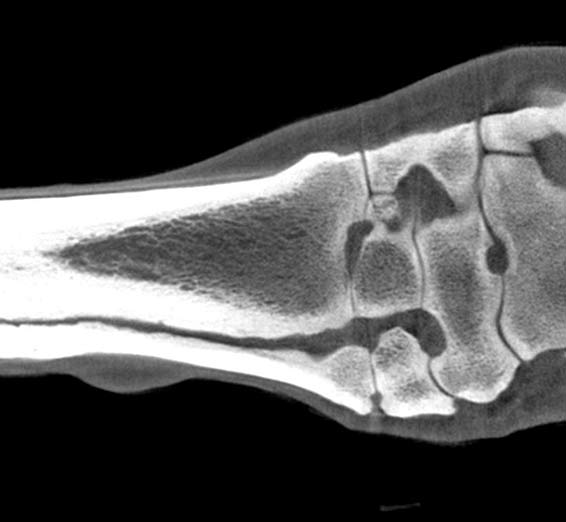

DUAL ARM ROBOTIC MULTIMODALITY SYSTEM FOR EQUINE APPLICATIONS

Making tomographic scans of standing horses with minimal sedation. The video demonstrates the efficiency of Orimtech motion compensation technology: sharp extremity 3D CT image acquired from the standing and moving horse. Digital radiography and fluoroscopy acquisition and image processing specifically optimized for equine applications

read more about EDAMIS...ORIMTECH SOLUTIONS SUPPORT IMAGING OF MOVING OBJECTS

Registration and compensation of sporadic motion.

In equine scanning applications: no anesthesia, light sedation only, high-resolution 3D images without motion artifacts.